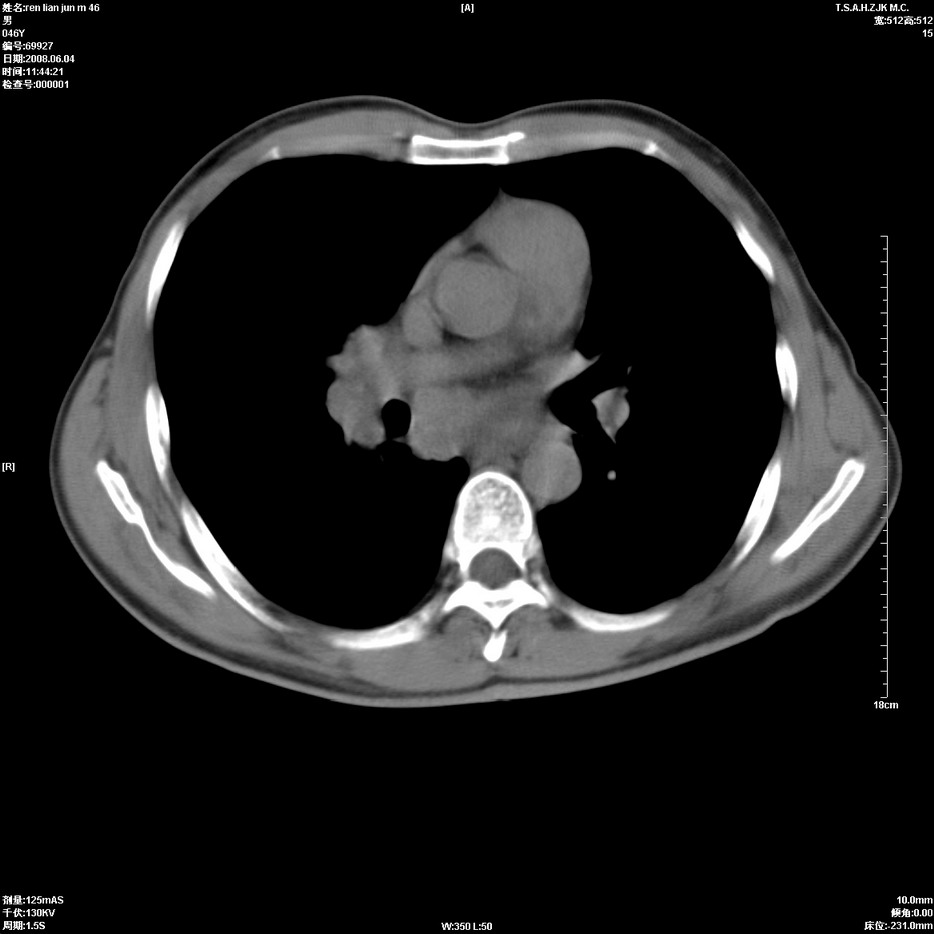

以下是引用qiu999在2008-6-5 17:14:00的发言:[br]考虑右肺中心型肺癌.颅内应做增强检查.

以下是引用形影不离在2008-6-5 19:18:00的发言:[br]右肺中心型肺癌并纵隔及左侧腋窝淋巴结转移,颅内应做增强检查。

以下是引用杀毒软件在2008-6-5 18:33:00的发言:[br]支持考虑右肺中心型肺癌,颅内病变是不是转移,不好说